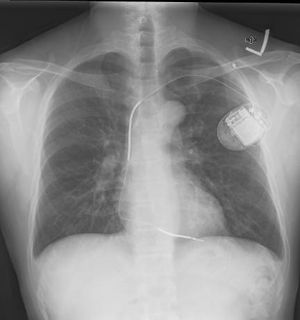

مزيل الرجفان المغروس

بعد النجاة من الرجفان البطيني فإن المرضى الذين عانوا من الرجفان البطيني لأسباب غير رجعية يجب حمايتهم من تكرار الرجفان البطيني عن طريق غرس جهاز مزيل الرجفان المغروس إنگليزية: ICD or implantable cardioverter defibrillator. هذا الجهاز شبيه بناظم الخطى، ويقوم بمراقبة مخطط القلب الكهربائي وتحليله، يقوم الجهاز بتوجيه صدمة كهربية للقلب عن طريق أقطاب مغروسة حول القلب منهياً بذلك الرجفان البطيني.